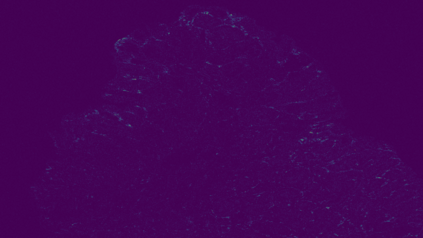

The usage of chemical imaging technologies is becoming a routine accompaniment to traditional methods in pathology. Significant technological advances have developed these next generation techniques to provide rich, spatially resolved, multidimensional chemical images. The rise of digital pathology has significantly enhanced the synergy of these imaging modalities with optical microscopy and immunohistochemistry, enhancing our understanding of the biological mechanisms and progression of diseases. Techniques such as imaging mass cytometry provide labelled multidimensional (multiplex) images of specific components used in conjunction with digital pathology techniques. These powerful techniques generate a wealth of high dimensional data that create significant challenges in data analysis. Unsupervised methods such as clustering are an attractive way to analyse these data, however, they require the selection of parameters such as the number of clusters. Here we propose a methodology to estimate the number of clusters in an automatic data-driven manner using a deep sparse autoencoder to embed the data into a lower dimensional space. We compute the density of regions in the embedded space, the majority of which are empty, enabling the high density regions to be detected as outliers and provide an estimate for the number of clusters. This framework provides a fully unsupervised and data-driven method to analyse multidimensional data. In this work we demonstrate our method using 45 multiplex imaging mass cytometry datasets. Moreover, our model is trained using only one of the datasets and the learned embedding is applied to the remaining 44 images providing an efficient process for data analysis. Finally, we demonstrate the high computational efficiency of our method which is two orders of magnitude faster than estimating via computing the sum squared distances as a function of cluster number.